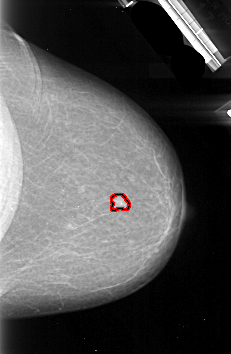

A_1093_1.LEFT_MLO

LEFT_MLO LINES 5341 PIXELS_PER_LINE 2941 BITS_PER_PIXEL 16 RESOLUTION 42 NON_OVERLAY

FILE: A_1093_1.RIGHT_MLO.OVERLAY

TOTAL_ABNORMALITIES 1

ABNORMALITY 1

LESION_TYPE MASS SHAPE IRREGULAR MARGINS SPICULATED

ASSESSMENT 5

SUBTLETY 4

PATHOLOGY MALIGNANT

TOTAL_OUTLINES 2

BOUNDARY

CORE